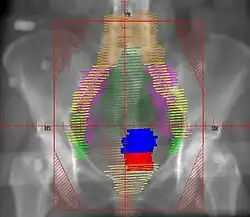

RT Technique

Example of an AP radiation therapy treatment field for Stage IB2+ Cervix used at Tufts/Brown residency program. Actual patient contours should guide field design.

• Superior border: L4/L5. If common illiac LN involvement, superior border should extend to L3/L4 or higher to cover the disease with 3 cm margin

• Inferior border: inferior edge of pubic ramus. If vaginal involvement, inferior border should extend 3-4 cm past the vaginal extent of the disease, as marked by a gold seed

• Lateral borders: ~2cm lateral to bony pelvis, in order to cover lymph nodes

• Red: cervix; Blue: uterus; Khaki: bladder; Brown: rectum

• Orange: common illiac LNs; Yellow: external illiac LNs; Light Green: obturator LNs; Purple: internal illiac LNs; Dark Green: presacral LNs